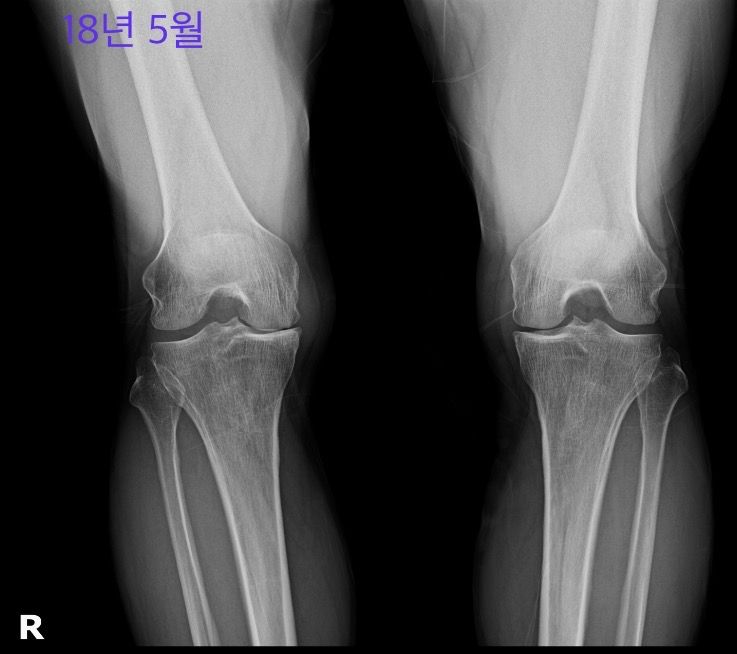

사진은 18년 5월, 18년 12월, 24년 5월입니다.

• 1번 째 사진

우측 무릎은 18년 5월부터 이미 진행이 많이 되어있는 상태이고 18년 12월에는 관절간격이 조금 더 넓은것처럼 보이지만 현재 grade 4로 보입니다.

좌측은 18년 5월에 우측보다는 가볍지만 grade 3이라고 생각되며 현재 grade 3-4 정도로 보입니다.